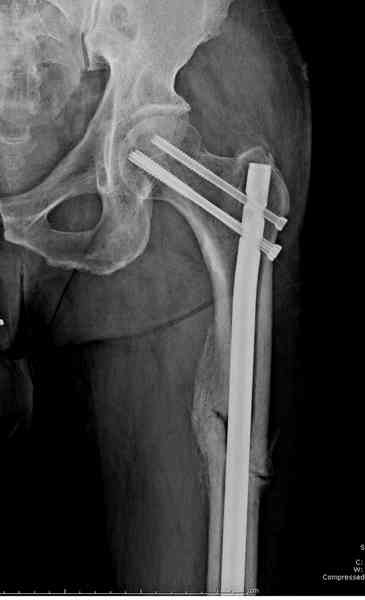

В первый же день произведено антеградное штифтованием DePuy Trochanteric Nail.

и проведены шурурпы через и спереди штифта без удаления.

Послеоперационные снимки